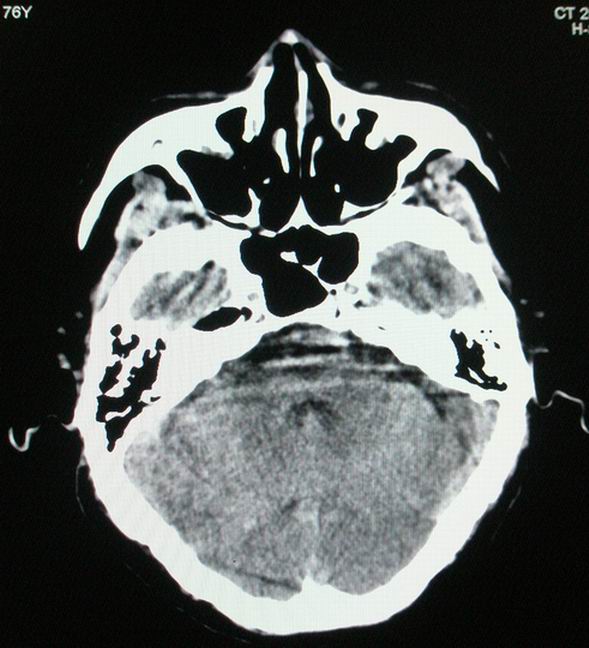

以下是引用随光逐影在2008-4-5 7:46:00的发言:[br]1)考虑为:多发性脑转移瘤。建议:行进一步检查。2)多发性腔隙性脑梗塞。3)脑白质病。4)脑萎缩。

以下是引用zjzjr在2008-4-5 9:00:00的发言:[br]1.双侧颞叶占位性病变,考虑为转移瘤可能性大。[br]2.左侧基底节区陈旧性腔隙性脑梗塞。[br]3.脑白质病。建议mri进一步检查。

以下是引用xuhuihong在2008-4-5 0:59:00的发言:[br]1.双侧颞叶占位性病变,考虑为转移瘤可能性大。[br]2.左侧基底节区陈旧性腔隙性脑梗塞。[br]3.脑白质病。建议mri进一步检查。

以下是引用形影不离在2008-4-4 23:29:00的发言:[br]1.双侧颞叶占位性病变,考虑为转移瘤可能性大。[br]2.左侧基底节区陈旧性腔隙性脑梗塞。[br]3.脑白质病。